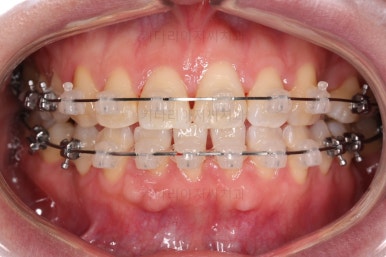

브라켓을 부착합니다.

이번 환자분이 선택하신 장치는 데이몬 클리어라고 하는 자가결찰 세라믹 장치인데요.

일반적으로 흔히 아시는 클리피씨 장치에 비해서 철사를 잡아주는 뚜껑까지 세라믹으로 되어 있어서 아마도 현존하는 세라믹 장치 중에서는 가장 심미적인 장치라고 볼 수 있습니다.

대신, 세라믹으로 되어 있다보니 강도 때문에 부피는 조금 더 커진다는 단점은 있긴 합니다.

장치 부착 직후의 웃는 모습과 입이 좀 더 나오는 양상을 참고해 주시고요.

참고로 입이 나오는 정도는 사람마다 매우 달라서 데이몬 클리어는 이정도 나온다는 기준은 딱히 없긴 합니다.